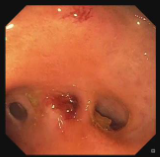

Cholangiogram through choledochoduodenostomy revealed multiple filling defects located mostly in liver segment IV. Extraction of many stones was achieved using a SpyGlass™ Retrieval Basket through 18 Fr gastroscope. Segment IV takeoff was dilated to 8 mm using a through the scope balloon. Cholangioscopy using SpyScope™ DS through therapeutic gastroscope with cap was performed revealing many remaining intraductal stones (Figure 3). Extraction of stones with SpyGlass Retrieval Basket enabled complete clearance of segment IV stones (Figure 4, 5).